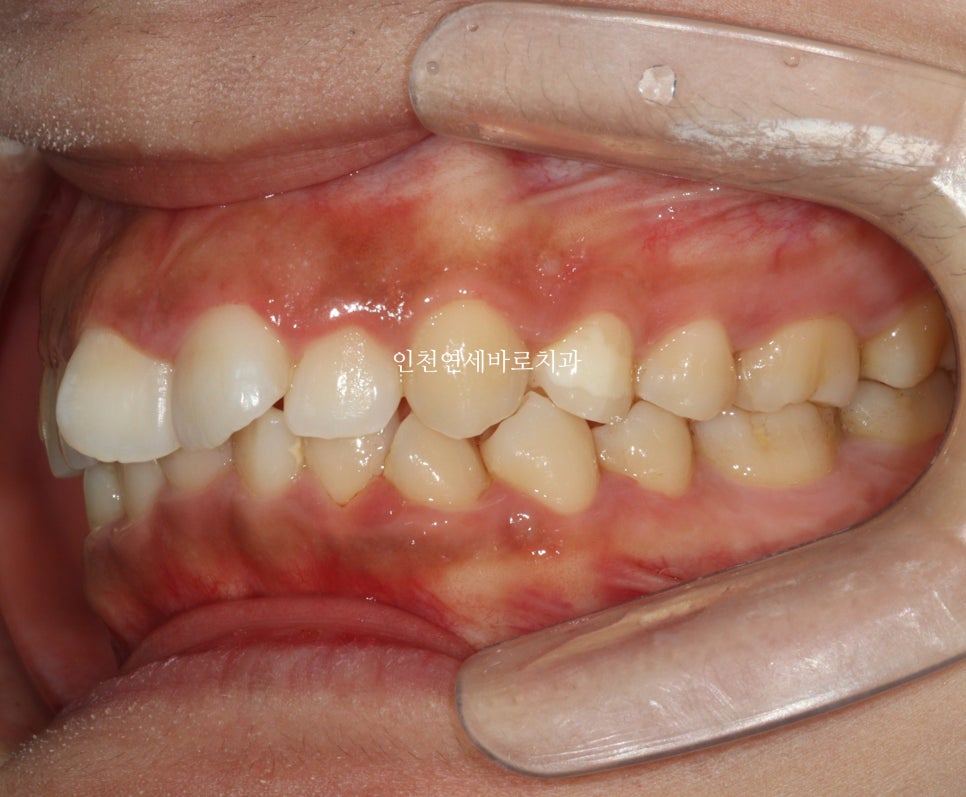

전후 비교입니다

전 후 교합의 비교입니다.

안정적으로 교합이 형성되었습니다

교정 끝난 직후의 사진이라 아주 약간은 제 마음에 안드는 부분이 있지만

11월말에 내원하시어 #비베라 제작을 할때 체크해보면 모두 해결이 되어있을 겁니다.